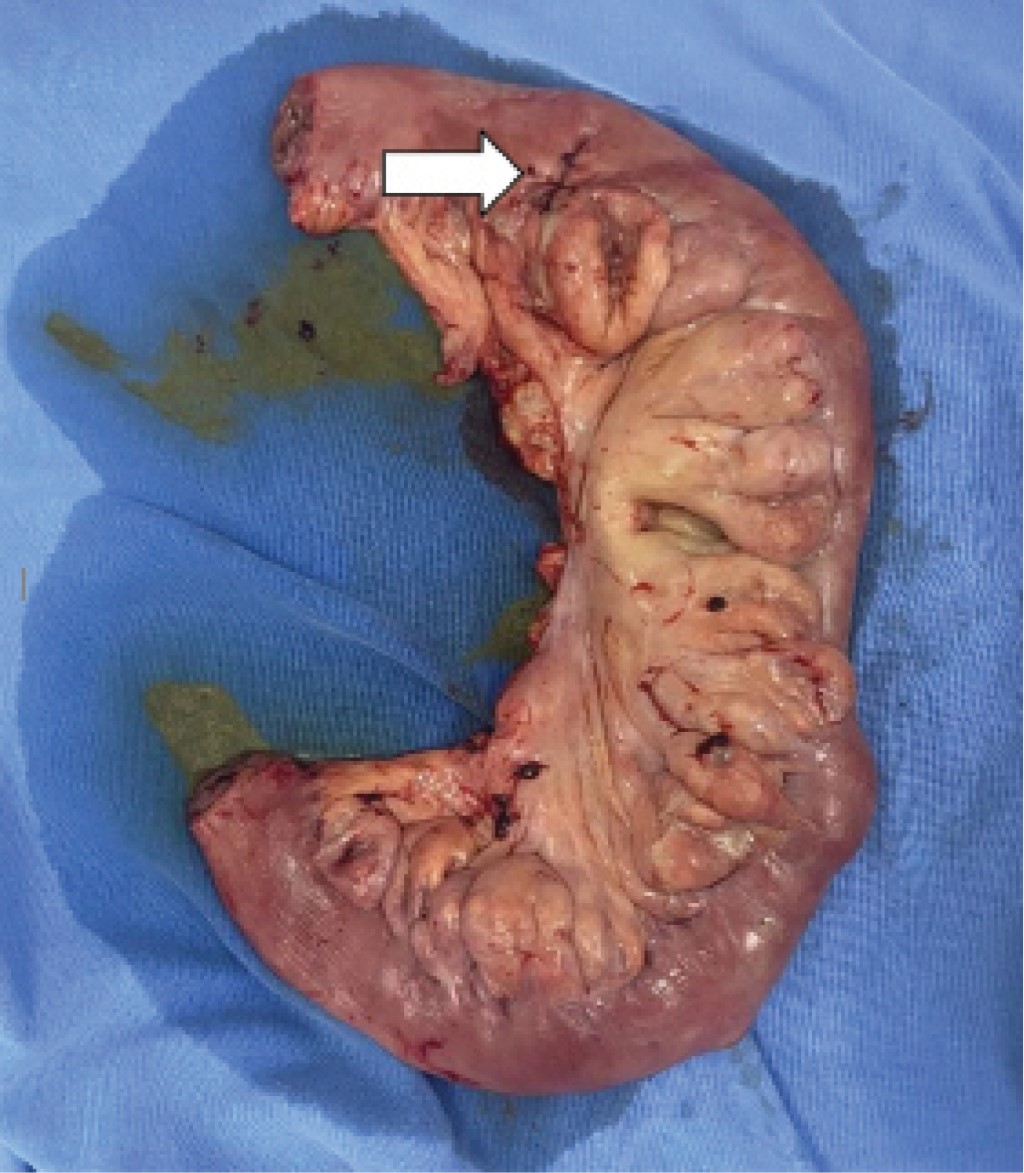

Exploratory laparotomy was performed, where 1,000 ml of free intestinal fluid in the cavity, intestinal loops with fibrin plaques, perforation of 1 cm in a jejunal diverticulum of approximately 6 × 4 cm, 50 cm from the angle of Treitz, with multiple diverticula in about 80 cm of the jejunum perforation were seen. Initially, primary closure was performed, and then intestinal resection of approximately 90 cm, with jejunum-jejunum end-terminal anastomosis in two planes.

The histopathological report corroborated the clinical diagnosis, showing a thin wall with congestion and perforated diverticular disease leading to acute peritonitis (Figures 3, 4, 5, 6 and 7).

Figure 1